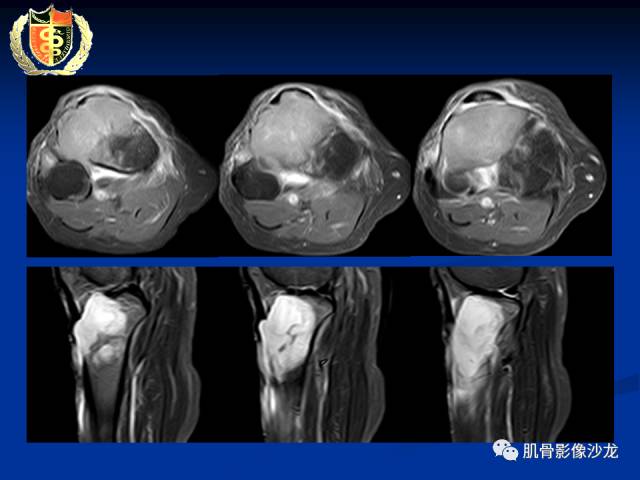

骨淋巴瘤及软骨肉瘤两例CT及MR影像表现

各位老师,磁共振图像是增强检查,最后一张是DWI图像[愉快]

胫骨近端骨质破坏,边缘不清,破坏边模糊,骨皮质不完整,可见软组织肿块突破骨皮质外,病灶累及关节面下,无关节内累及,MRI病灶呈T2WI高信号,信号均匀,考虑:恶性肿瘤性病变,淋巴瘤先考虑,转移瘤及其他待排

内部密度和信号比较均匀,无钙化,无骨膜反应,骨质破坏边缘不清晰,软组织较明显,弥散受限,首先不能排除淋巴瘤